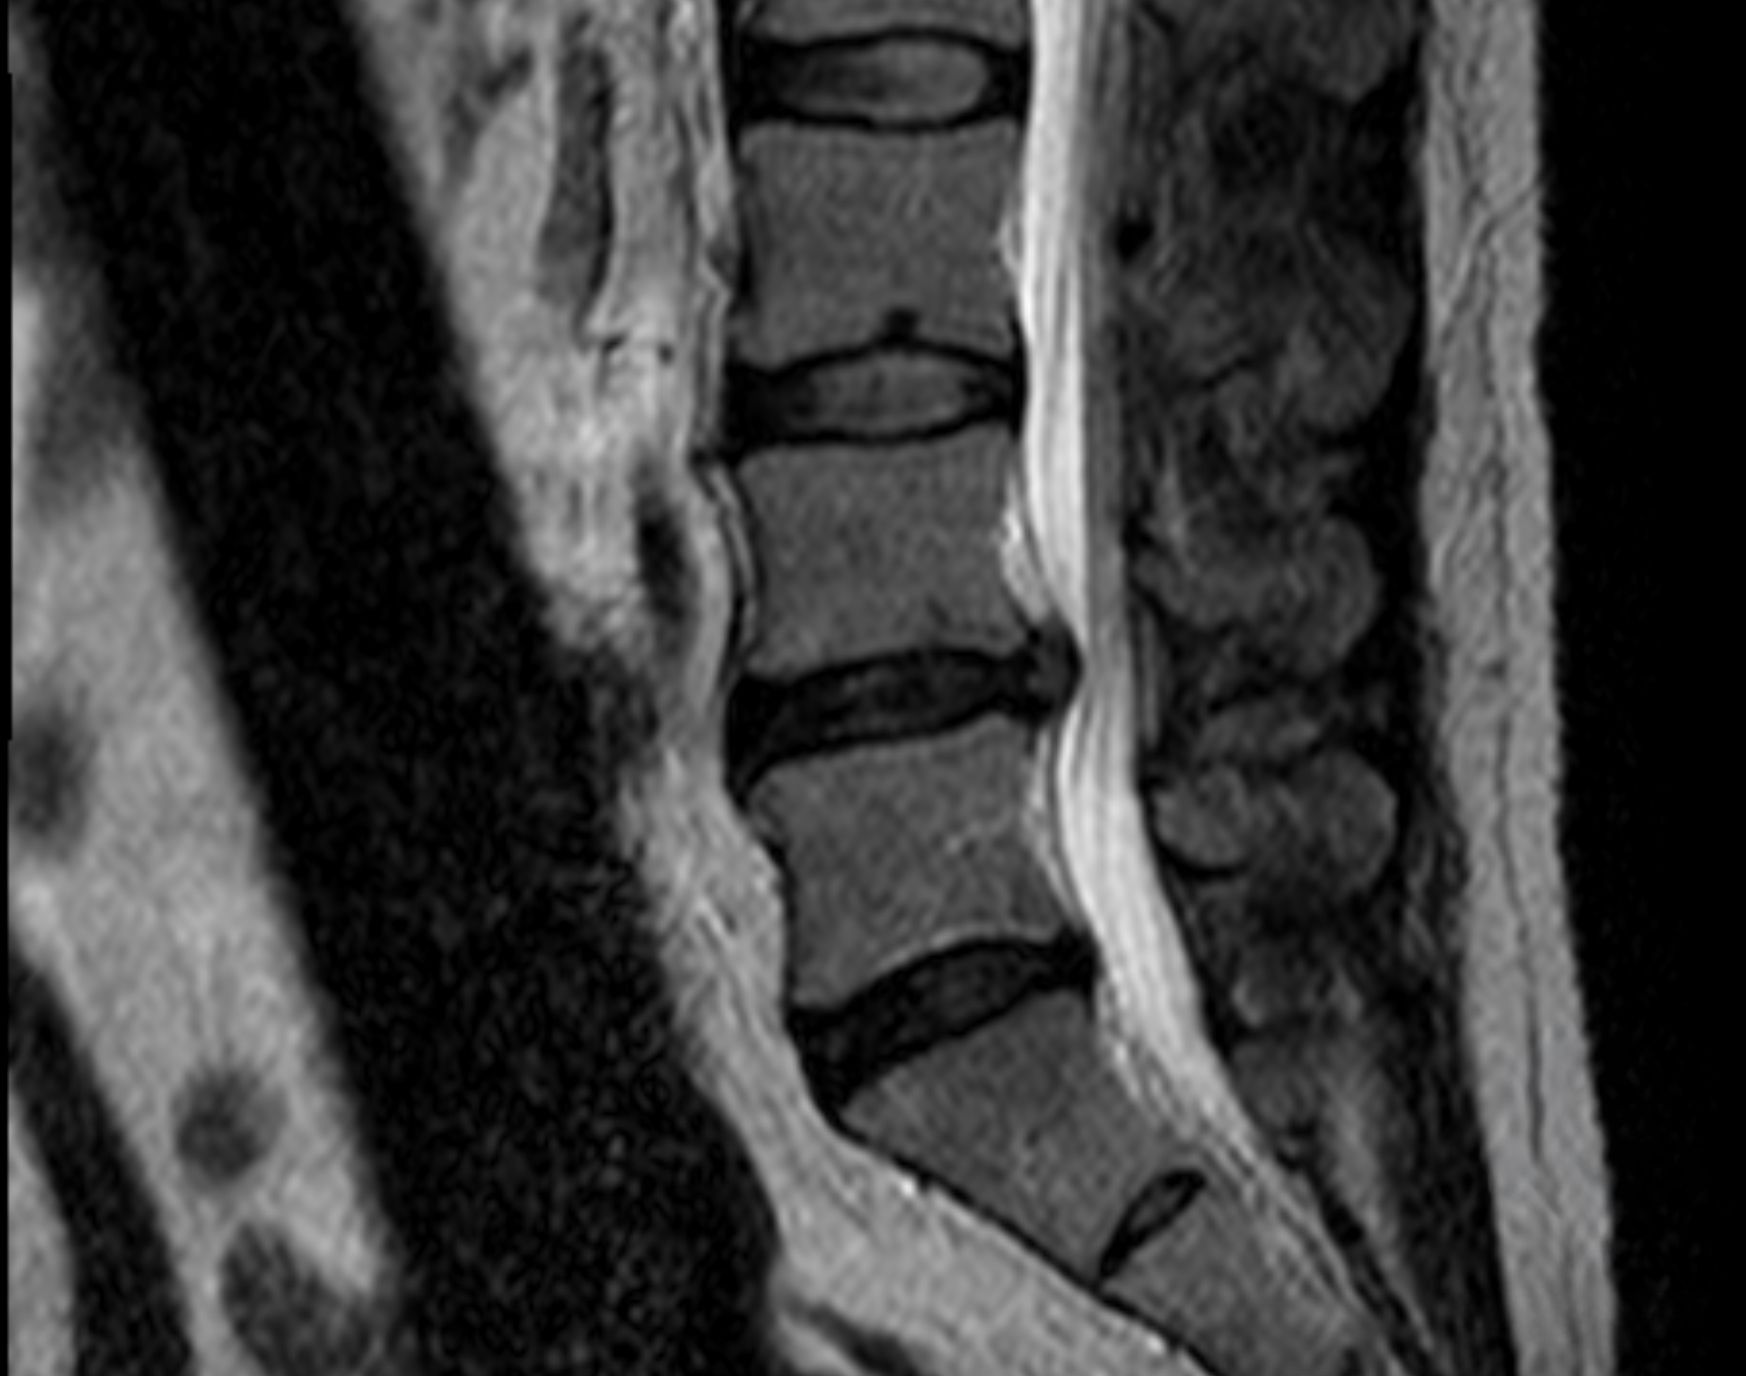

Cas clinique 3

Diagnostic

Bonjour, je suis.